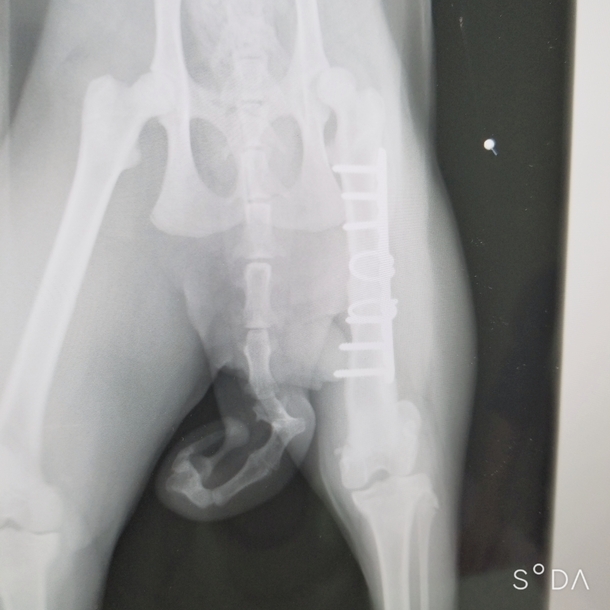

1ヶ月検診の

レントゲン画像です。

見事に骨がまとまっていました!

あとは、無理させずに、

ゴーの可能性を信じるだけです!!